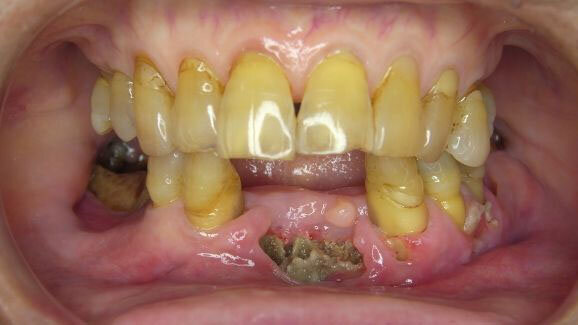

KYOTO, JAPAN – Bisfosfonaten, medicijnen die vaak worden gebruikt om botaandoeningen als osteoporose te behandelen, leiden mogelijk tot een verhoogd risico op een ernstige botontsteking van de kaak. Onderzoekers van de Universiteit van Kyoto ontdekten dat vooral oudere patiënten die bisfosfonaten intraveneus toegediend hadden gekregen vaker met osteonecrose van de kaak te maken kregen.

Onderzoekers ontdekten dat 42 maanden na de tandextractie de cumulatieve incidentie van osteonecrose van de kaak significant hoger was bij patiënten die bisfosfonaten hadden genomen. Vijf patiënten aan wie bisfosfonaten waren voorgeschreven ontwikkelden osteonecrose in de kaak, tegen slechts één patiënt in de controlegroep.

Er was een significant verschil wat betreft de leeftijd en prevalentie van kanker of osteoporose tussen de twee groepen. Het risico op osteonecrose van de kaak was een stuk hoger bij patiënten boven de 65 jaar die intraveneus bisfosfonaten toegediend hadden gekregen.

Ook bleek uit het onderzoek dat alveolair botverlies een risicofactor kan zijn voor bisfosfonaatgerelateerde osteonecrose van de kaak na tandextractie. De onderzoekers suggereren daarom dat ontsteking van het paradontale weefsel mensen vatbaar maakt voor bisfosfonaatgerelateerde osteonecrose. Een preventieve behandeling van orale bacteriën is volgens hen essentieel voor een gunstig resultaat van de tandextractie.